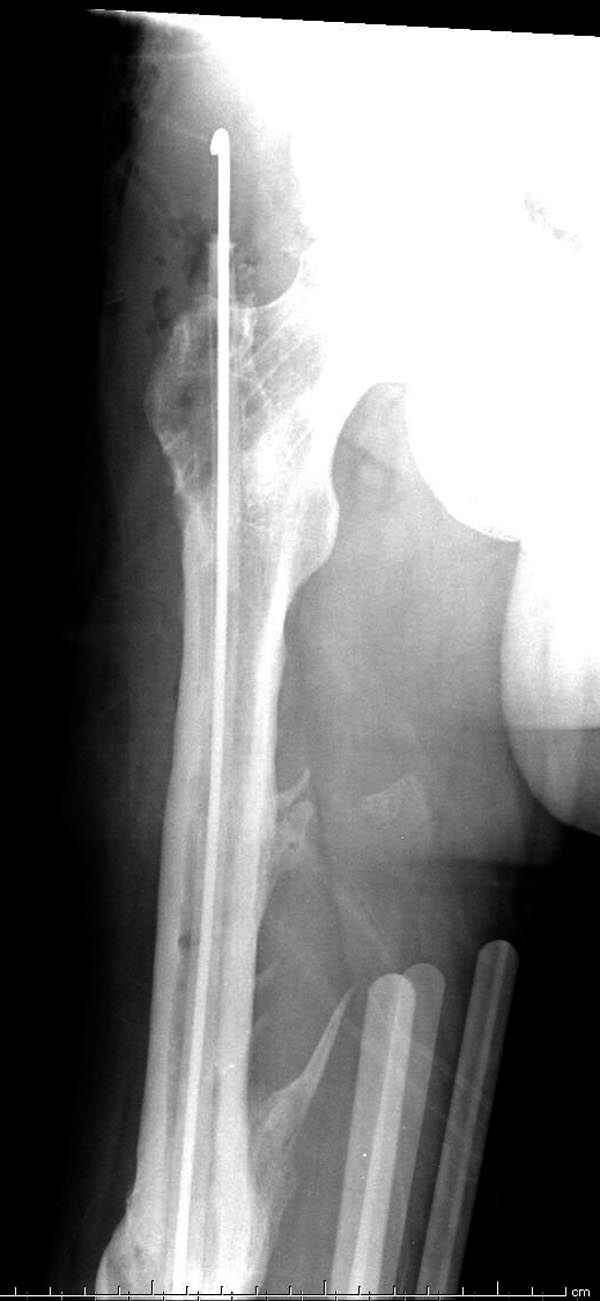

Мы не дождались “Happy End”, у больного IQ в пределах 70%, через 6 месяцев вернулся после небольшой травмы, споткнувшись получил перелом

того же бедра (рис №7).

На следующий день произвели интрамедуллярный остеосинтез: этапы во время операции (рис №8, №9)

и последующих снимках (рис №10, 11, 12, 13) перелом сростается и передвигается с полной нагрузкой.